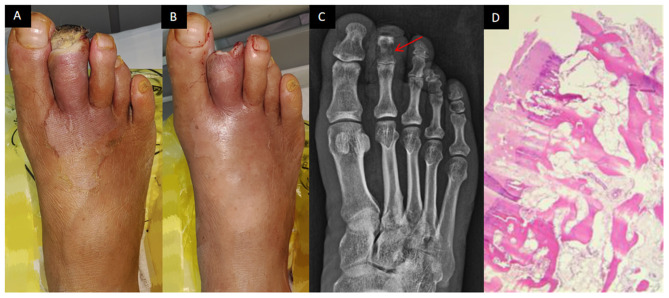

Abstract Image